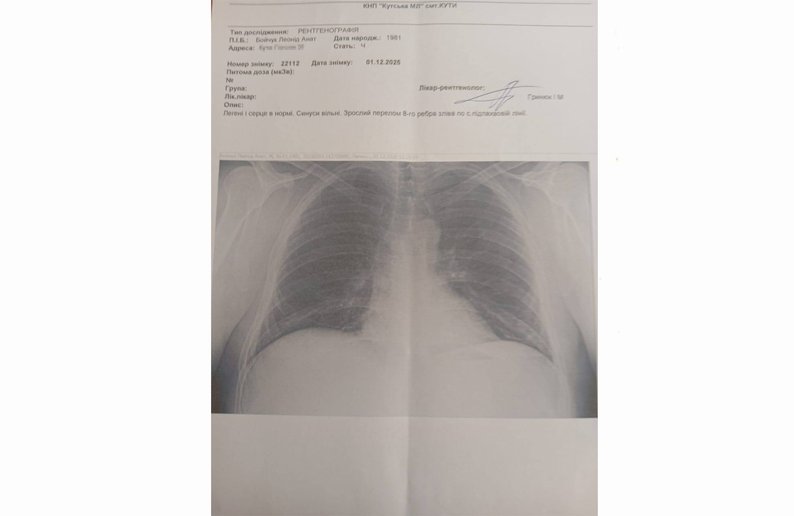

Спочатку мені зробила жінка кардіограму. І після цього "айтівець" та Анатолій Ч. повели мене на флюорографію. Сказали: "Роздягайся". Я відповів, що у 2024 році хворів на гострий бронхіт, і в Кутській лікарні мені робили флюорографію на новому апараті. Двічі — до хвороби і після. Просив їх зробити запит через Helsi», — пригадує Леонід Бойчук.

Медики діагностували у Леоніда Бойчука перелом лівого ребра.